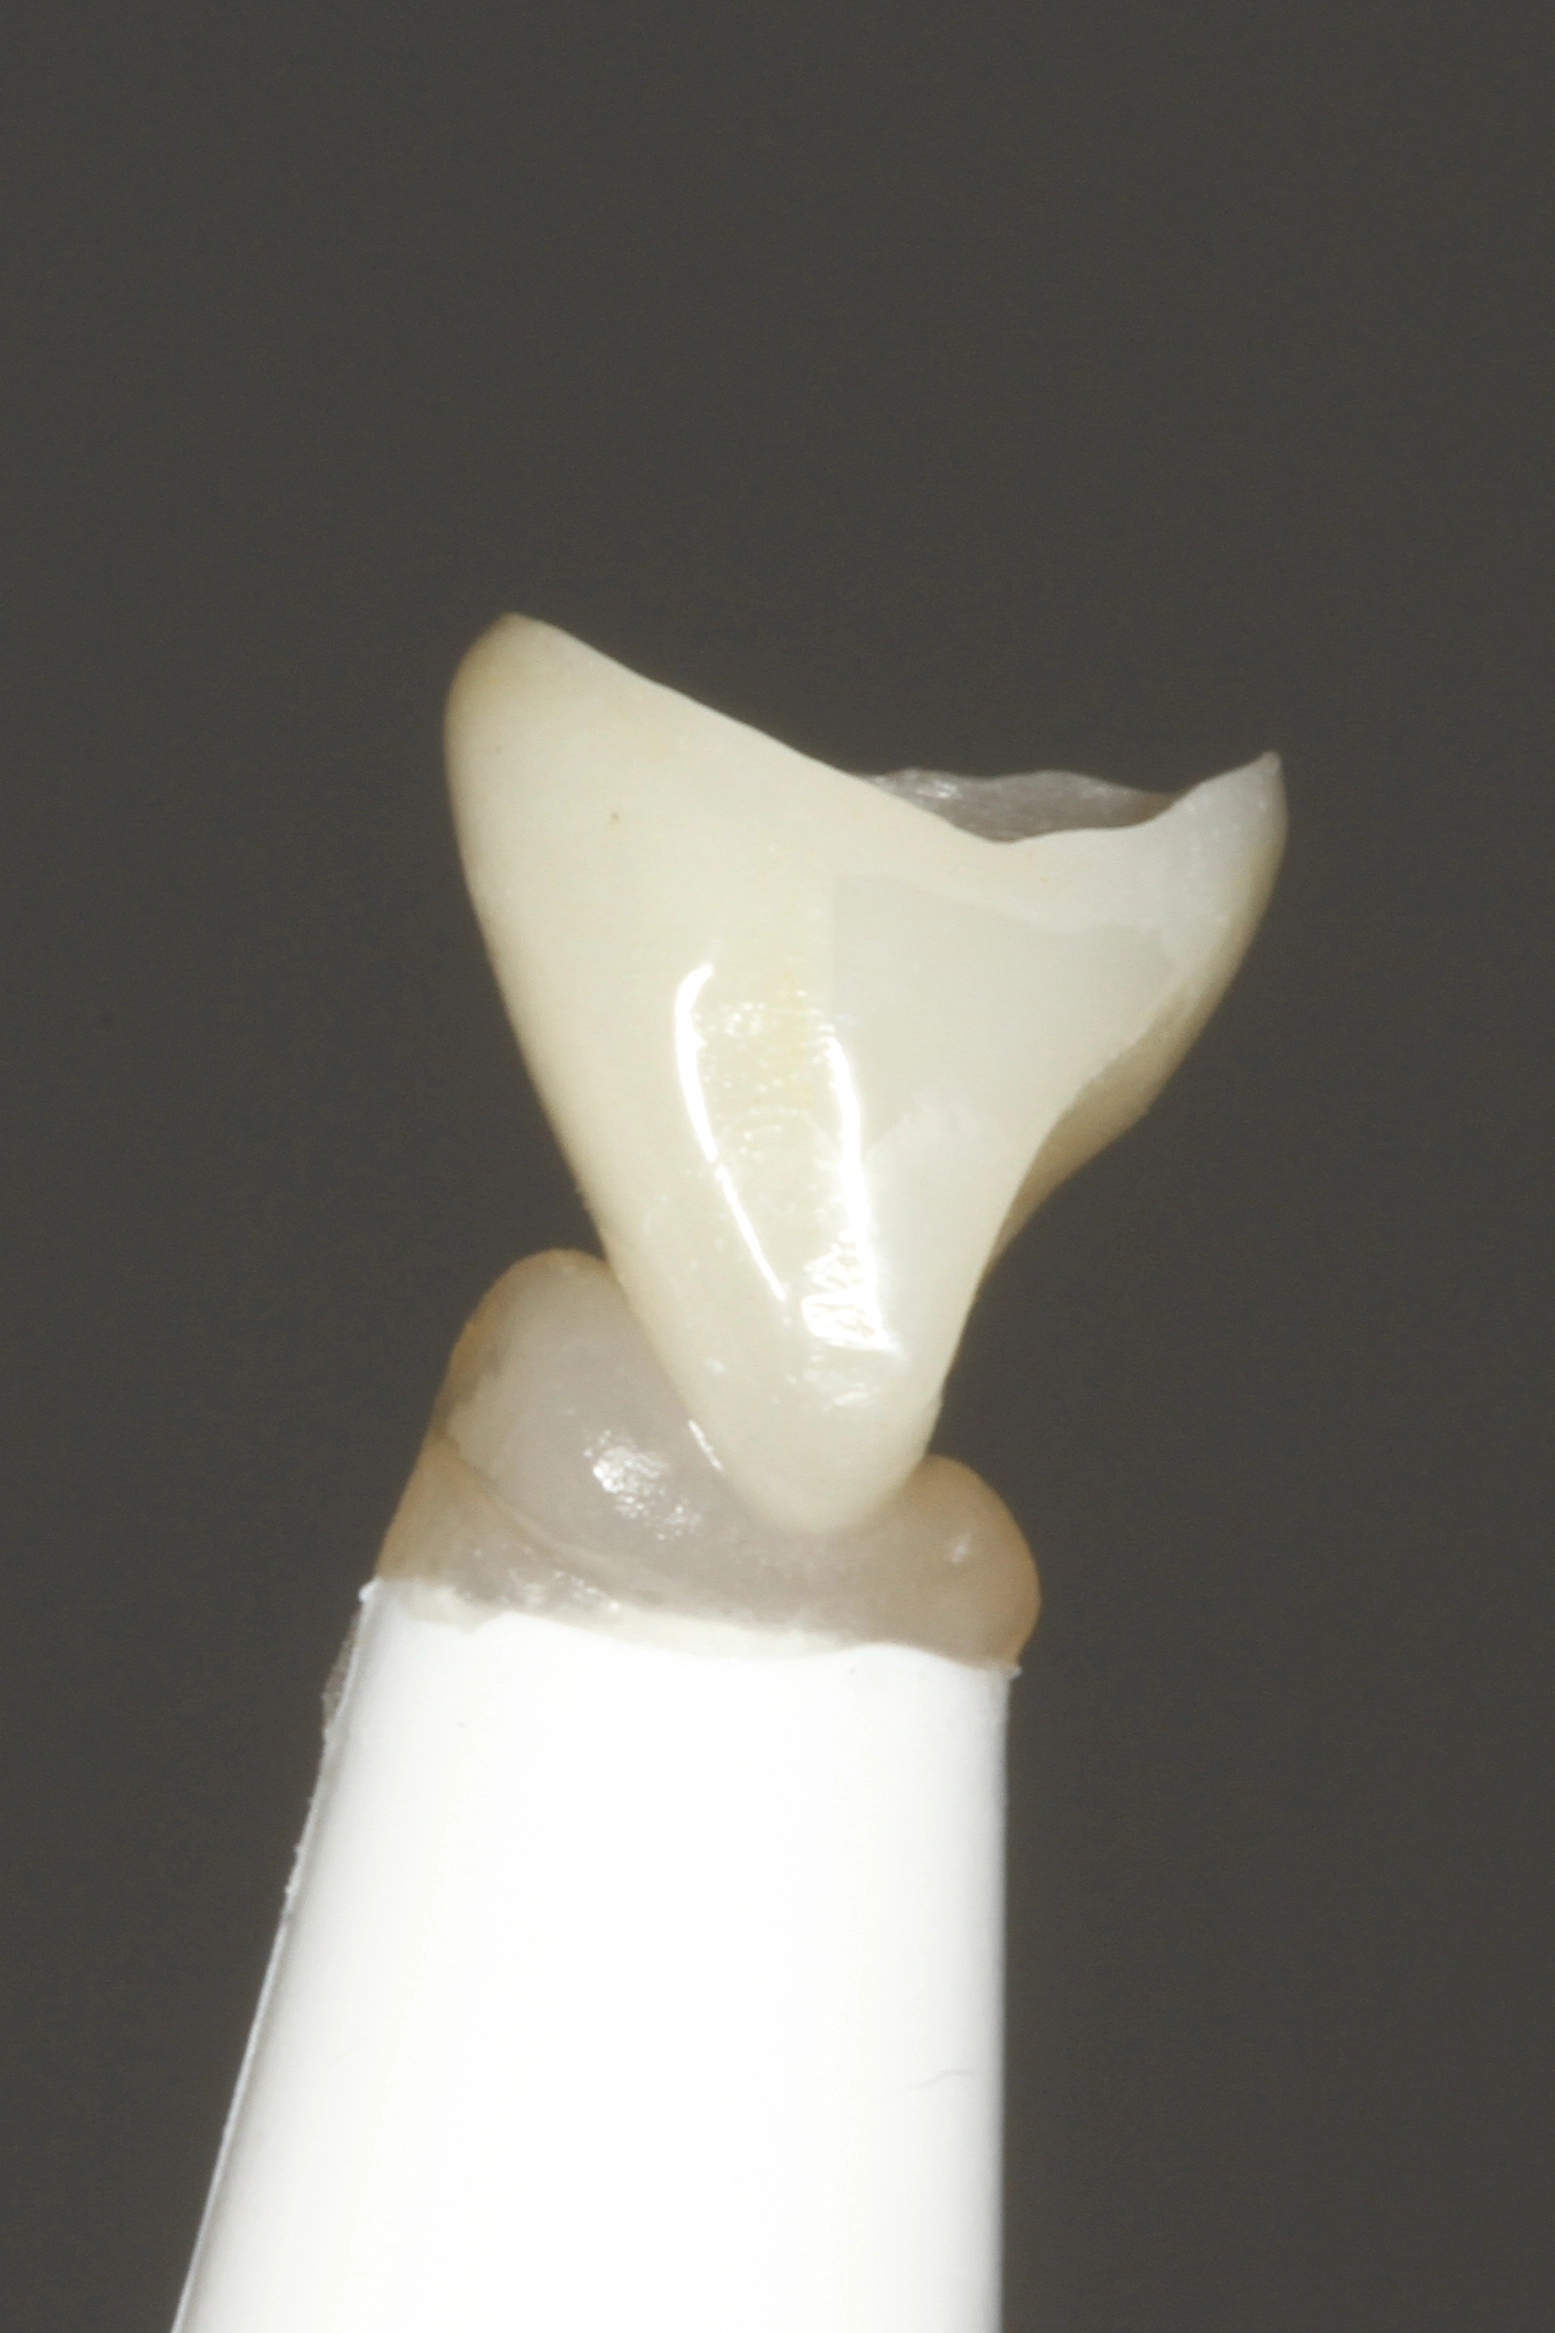

Die Abbildung 56 zeigt die Einprobe eines Glasfaserstiftes (EasyPost, Dentsply Sirona). Nach Vorbehandlung des Stiftes mit dem Visalys Restorative Primer und nach Reinigung des Kanalsystems mit AH Cleanser (Dentsply Sirona) sowie der Applikation des Visalys Tooth Primers im Zahn erfolgte die zeitgleiche Verklebung des Glasfaserstiftes mit Visalys CemCore (diesmal in der opaken Variante) und dem internen Aufbau des gesamten Zahnes. Die Abbildungen 57 bis 59 zeigen das 2-schichtige Einbringen von Visalys CemCore Opaque nach einer Zwischenhärtung des 1. Inkrements für 40 Sek., die Abbildung 60 die Röntgenkontrolle der Wurzelfüllung und des Stumpfaufbaus. Der okklusale Anteil der Kavität wurde wenige Minuten später von einem Kollegen okklusal reduziert und mit einem klassischen lichthärtenden Komposit definitiv versorgt.